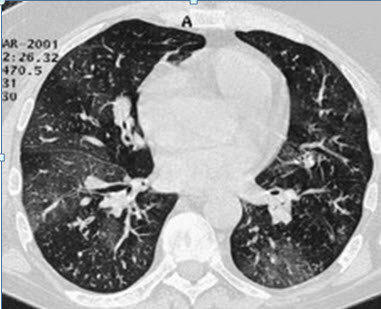

肺部結(jié)節(jié)是指肺部出現(xiàn)的圓形或不規(guī)則形狀的異常組織增生,通常通過(guò)醫(yī)學(xué)影像技術(shù)如X光、CT掃描等檢查發(fā)現(xiàn),肺部結(jié)節(jié)可能是良性的,也可能是惡性的,其形成原因多種多樣,包括感染、炎癥、良性腫瘤和肺癌等。